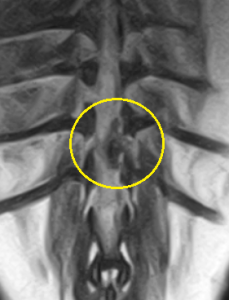

下の写真はのMRIでの椎間板ヘルニアの見え方の一例です。黄色丸の中にヘルニアを起こしている圧迫物質が「黒い影」として映っています。前後を走る白い棒状の脊髄神経を右下から重度に圧迫して、まるで押しつぶしているような画像が見られます。左写真がサジタル像(側面像)、右写真がコロナル像(水平の縦切り像)です。

実は、上のMRIの画像は上に示したレントゲン写真と同じ患者さんの全く同じ部位を撮影したものです。どうでしょうか?MRIの特長がなんとなくお分かりになりましたでしょうか。。。

MRIではさらに、ヘルニアを起こしている部位の特定だけではなく、周囲の脊髄神経の出血や炎症の存在、腫瘍や脊髄梗塞など、椎間板ヘルニア以外の病気の可能性を除外します。特にMRIは神経を画像で評価する能力に優れており、炎症による障害の程度や椎間板ヘルニアに伴う致命的な脊髄軟化症の診断をすることができます。